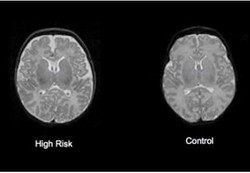

Dengan bertambahnya usia, orang akan mengalami kematian sel otak yang terjadi setiap harinya. Kematian otak ini tidak dapat dicegah meski bisa diperlambat. Berapa rata-rata sel otak yang mati per hari?